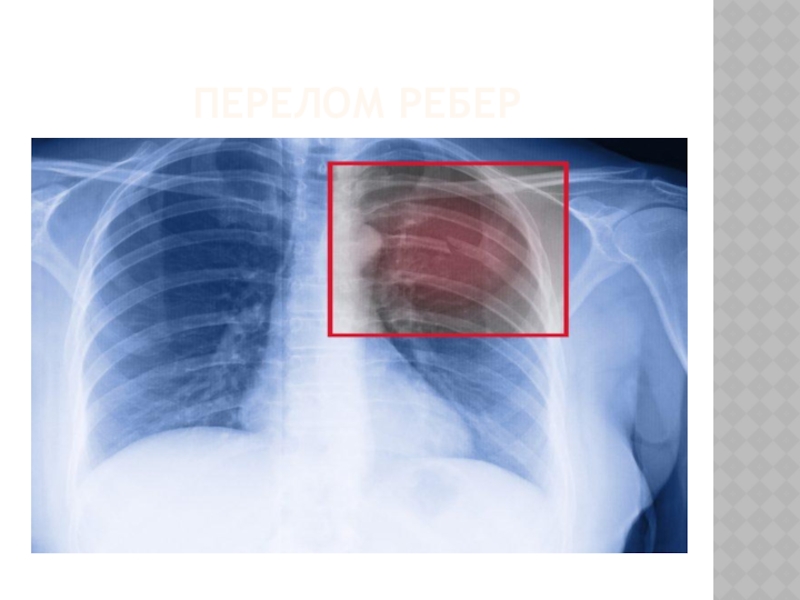

Слайд 24ПЕРЕЛОМ РЕБЕР

ПЕРЕЛОМ РЕБЕР

Слайд 25ОКАЗАНИЕ ПЕРВОЙ МЕДИЦИНСКОЙ ПОМОЩИ ПРИ

ПЕРЕЛОМЕ РЕБЕР

Дать пострадавшему обезболивающее средство

Наложить тугую

бинтовую повязку на грудную клетку, делая первые ходы бинта в состоянии выдоха. При отсутствии бинта можно использовать полотенце, кусок ткани или простыню

Придать пострадавшему возвышенное положение в положении сидя (полулежа)

ОКАЗАНИЕ ПЕРВОЙ МЕДИЦИНСКОЙ ПОМОЩИ ПРИПЕРЕЛОМЕ РЕБЕРДать пострадавшему обезболивающее средство Наложить тугую бинтовую повязку на грудную клетку, делая